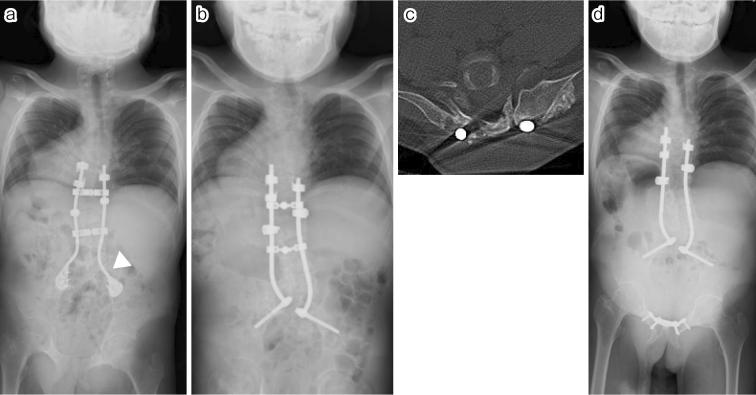

Case 1. A 10-year-old male underwent T8-S posterior fixation followed by multiple augmentations using allografts at the lumbosacral junction for delayed union. All additional procedures with bone graft using a posterior approach failed to achieve bone union; however, additional rigid fixation at the pubic symphysis resulted in a successful lumbosacral bone union. Case 2. A 6-year-old male underwent vertical expandable prosthetic titanium rib (VEPTR) surgery with multiple rod extension procedures. Subsequently, at the age of 10 years, a combined two-stage anterior (L1-3) and posterior (T8-iliac) fixation with T9 hemivertebrectomy was performed. As a result of subsequent nonunion with screw loosening, additional rigid fixation at the pubic symphysis was performed 1 month after posterior fixation. Bone union was finally achieved 1 year after all the surgical interventions.

病例1。一名10岁男性接受了T8 - S后路固定术,随后在腰骶部交界处使用同种异体骨进行了多次增强手术以促进延迟愈合。所有采用后路植骨的额外手术均未能实现骨愈合;然而,耻骨联合处的额外坚强固定导致腰骶部成功骨愈合。病例2。一名6岁男性接受了垂直可扩张人工钛肋骨(VEPTR)手术及多次棒延伸手术。随后,在10岁时进行了两阶段联合前路(L1 - 3)和后路(T8 - 髂骨)固定并进行了T9半椎体切除术。由于随后出现螺钉松动导致不愈合,后路固定术后1个月在耻骨联合处进行了额外的坚强固定。在所有手术干预1年后最终实现了骨愈合。